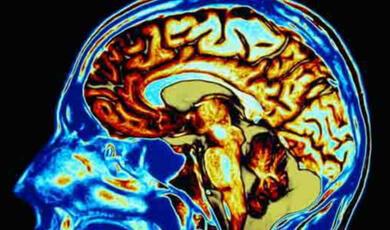

Professor Keith Kendrick is Systems and Behavioural Neuroscientist and was Gresham Professor of Physic between 2002 and 2006.

He has been a member of the Home Office's animal procedures committee and has worked at the University of Cambridge undertaking research with regards to how neural networks are organised to control recognition and responses to social and emotional cues. He is a fellow of the Institute of Biology and a member of the British Neuroscience Association.